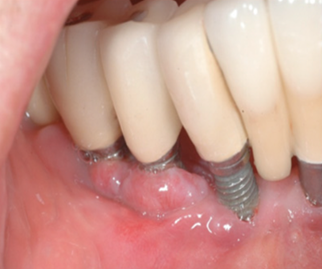

When replacing a missing tooth, bone loss within the socket can compromise esthetic and functional outcomes. For example, if you are considering implants, the compromised bone may not be strong enough to hold the implant, leading to metal exposure, food traps and ultimately loss of the implant.

Adding bone to the extraction socket helps to preserve the thickness, volume and density of the bone, allowing for more predictable implant placement and restoration.